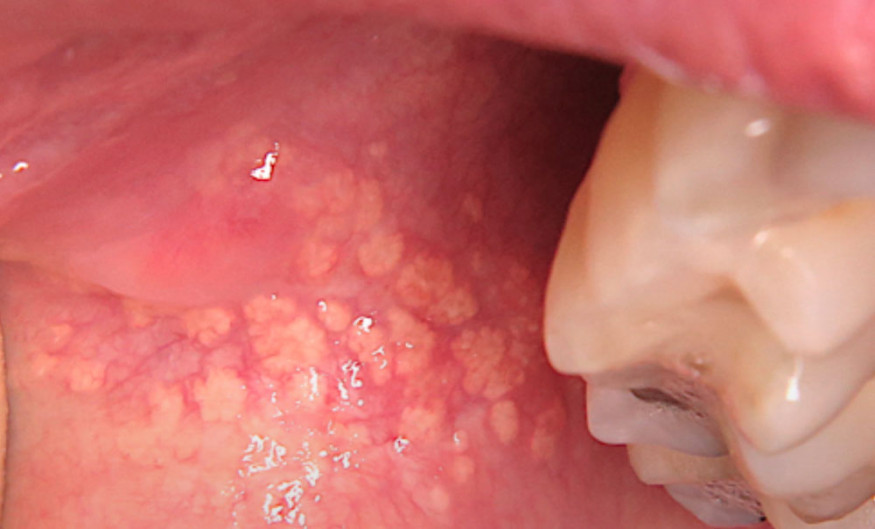

Il révélait au niveau de la joue gauche, à proximité de l’orifice du canal de Sténon, des papules jaunâtres, arrondies, de 1 à 2 mm de diamètre, organisées en chapelet. Sur la joue droite, on observait des papules d’aspect similaire.

Le tableau clinique était caractéristique de granulations ou grains de Fordyce. Les grains de Fordyce sont des glandes sébacées hétérotopiques qui ont migré dans la muqueuse buccale au cours de la période embryonnaire. Contrairement à la peau, ces glandes sébacées ne sont pas annexées à un follicule pileux. Elles concernent 80 à 95 % de la population. Elles apparaissent visibles le plus souvent à l’adolescence, en lien avec les modifications hormonales.

Les granulations de Fordyce peuvent se localiser sur la muqueuse buccale (joues et lèvres principalement), mais aussi sur la muqueuse génitale (face interne du prépuce, petites lèvres). Elles doivent être considérées comme des variations physiologiques et acceptées comme telles par les patients. Dans de rares cas, le préjudice esthétique peut amener à proposer un traitement ablatif par laser CO2 ou hyfrécation. Les rétinoïdes utilisés dans le traitement de l’acné…